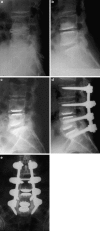

A retrospective clinical-radiological study to evaluate the long-term outcome after artificial disc replacement was performed. The objective is to investigate long-term results after implantation of a modular type artificial disc prosthesis in patients with degenerative disc disease (DDD). Total disc replacement (TDR) is a surgical procedure intended to save segmental spinal function, and thus replace spondylodesis. Short-term results are promising, whereas long-term results are scarce. The Charité TDR is the oldest existing implant, therefore, the longest possible follow-up is presented here. Seventy-one patients were treated with 84 Charité TDRs types I-III. Indication for TDR was moderate to severe DDD. Fifty-three patients (63 TDRs) were available for long-term follow-up of 17 years. Evaluation included Oswestry disability index, visual analog scale, overall outcome score, plain and extension/flexion radiographs. Implantation of Charité TDR resulted in a 60% rate of spontaneous ankylosis after 17 years. No significant difference between the three types of prostheses was found concerning clinical outcome. Reoperation was necessary in 11% of patients. Although no adjacent segment degeneration was observed in the functional implants (17%), these patients were significantly less satisfied than those with spontaneous ankylosis. TDR, nowadays, is an approved procedure. Proof that long-term results of TDR implantation in DDD are at least as good as fusion results is still missing.